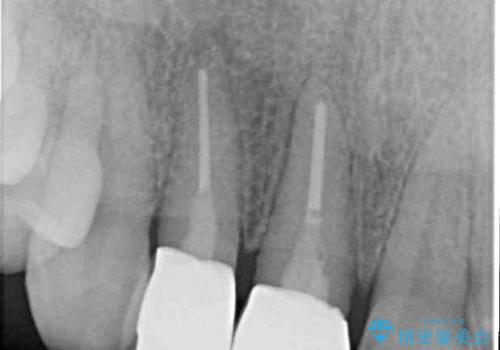

クラウンの状態は、根管治療の状態も含めて決して良い状態とは言えず、矯正治療後の根管治療と補綴治療の再治療を前提として、インビザラインによる矯正治療を行うこととしました。

矯正治療中に前歯2本のクラウンは外れてしまい、途中仮歯に替える必要があったので期間は掛かりましたが、歯列も整い、負担のかからない咬み合わせを達成することができました。